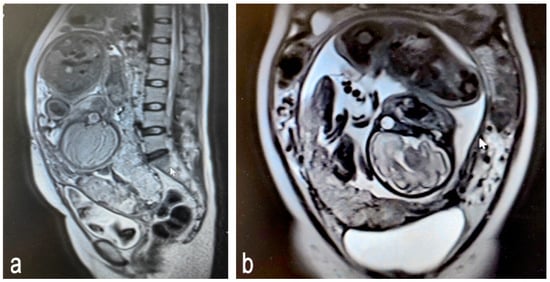

Figure 3.

Magnetic resonance images of placenta accreta spectrum (Prenatal stage): (a) sagittal plane; (b) frontal plane.

In the second and third trimesters, the placenta has fully developed, allowing MRI’s high resolution to accurately depict the depth and extent of placental invasion. Compared to ultrasound, MRI provides clearer anatomical structural information, thus revealing detailed relationships [36].The common features of PAS detected using MRI include the loss or blurring of the placenta–myometrium boundary: in cases of abnormal attachment or invasive implantation, the normal boundary (low signal line) between the placenta and myometrium becomes blurred or disappears completely. T2-weighted images show the loss of definition between the placenta and myometrium. Severe cases may show direct penetration through the myometrium (Figure 3).